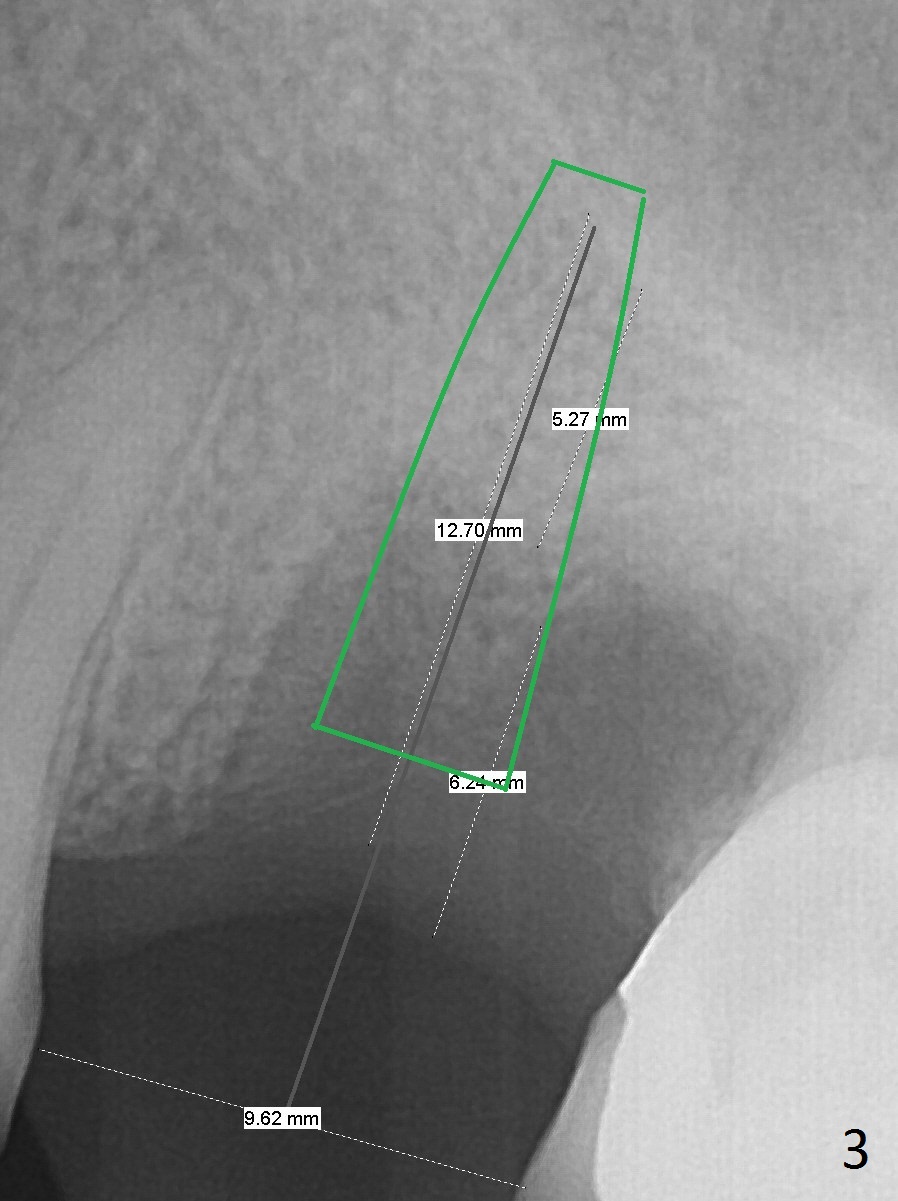

A 44-year-old woman will return to clinic for #14 implant placement 2.5 months post extraction (Fig.1).  The tooth used to have persistent fistula.  The bone density appears to be low coronally.  To compensate for the sloped sinus floor (arrowheads), start osteotomy as mesial as possible (Fig.2 red arrow) either with Magic Expander or Drill and place an implant as high as possible (Fig.3).  If there is buccal plate defect, place the implant as palatal and deep as possible.  Use Metronidazole routinely for sinus cases.